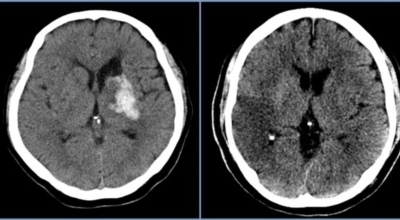

파킨슨병은 도파민 분비 신경 세포의 소실로 발생하는 질환으로 알려져 있는데요 도파민이란 뇌의 신경세포에서 만들어지는 물질로 세포와 세포 간의 신호를 전달하는데 이용되는 신경 전달 물질 중 한가지로 이 도파민이 감소함에 따라 파킨슨병이 걸린다고 하는데 이 도파민 세포가 떨어지는 이유는 아직 정확히 밝혀지지 않았다고 합니다.

일부 파킨슨 환자는 파킨슨병의 가족력이 있는 경우가 있으며 이런 가족들 중 일부에서는 유전자 이상이 발견되기도 해요. 그리고 일부유전적인 요인 이나 환경적인 요인으로 발병된는 것으로 알려져 있어요. 젊은 사람에게 발생하는 경우 유전적인 요인으로 볼수 있고 살충제 또는 제초제 개인 우물을 마시는등 독성물질 사용이 많은 농업종 사람들에게서 더 높은 파킨슨 병이 발병된는 것으로 알려져 있으나 이것역시 정확한 원인은 알수 없다고 합니다.